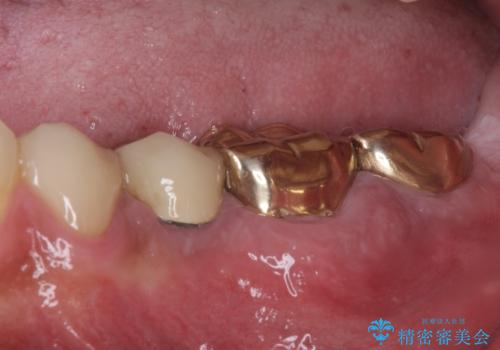

- 奥歯が割れてしまい、抜歯が必要となった患者様です。

以前にも歯が割れてインプラント治療を行いましたが、抜歯してからインプラント埋入→仮歯装着までに半年以上を要し、その間に残された歯への負担が大きくなり、セラミッククラウンが破折したことがありました。

そのため、当院に新しく導入した手法により、抜歯をした日にインプラントを埋入し、そのままを仮歯を装着することで、他の歯への負担を軽減する計画を立てました。